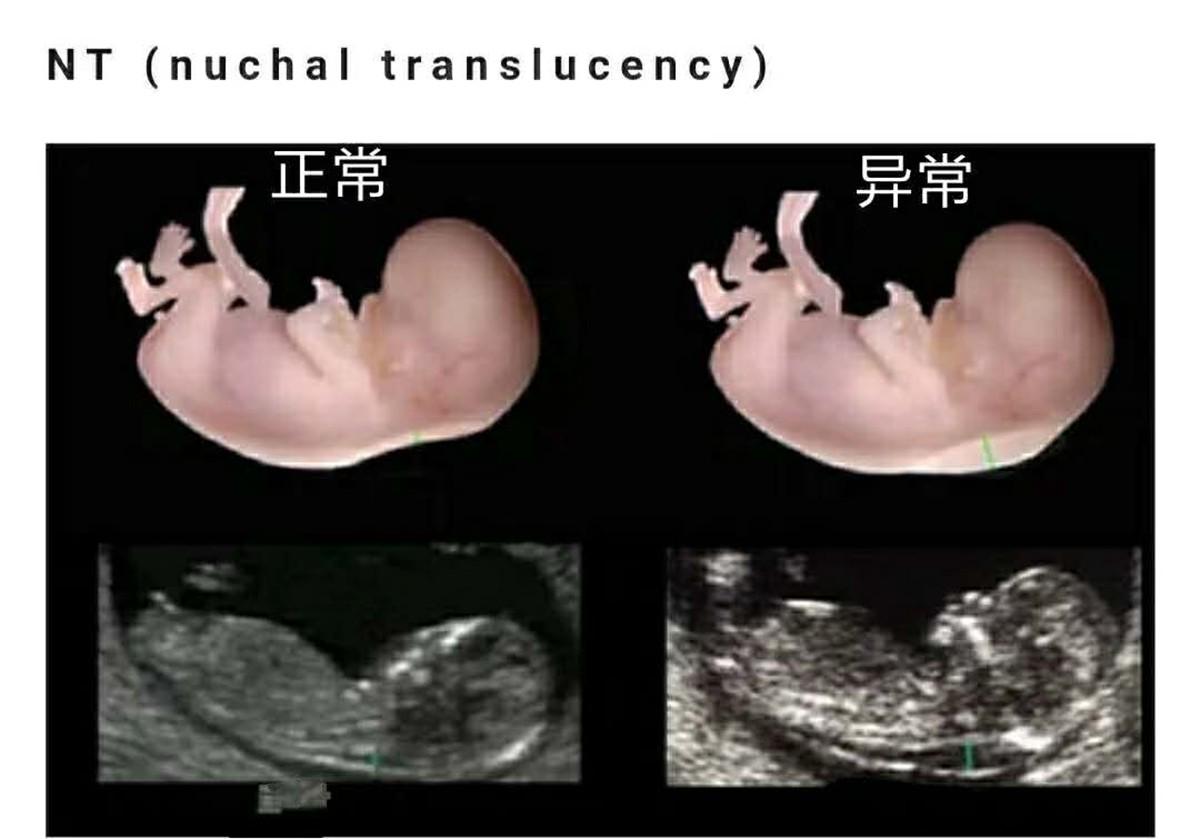

通过定期的产检,可以知道胎儿的胎心、血型等其他一些具体的情况。并且可以通过相关的检查,判断孩子是否有唐氏综合征或者是否患有畸形等其他情况。